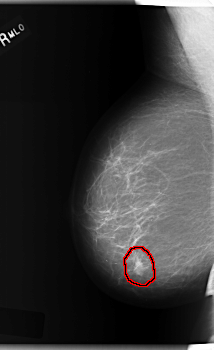

C_0209_1.RIGHT_MLO

FILE: C_0209_1.RIGHT_MLO.OVERLAY

TOTAL_ABNORMALITIES 1

ABNORMALITY 1

LESION_TYPE MASS SHAPE OVAL MARGINS MICROLOBULATED

ASSESSMENT 5

SUBTLETY 5

PATHOLOGY MALIGNANT

TOTAL_OUTLINES 1

BOUNDARY